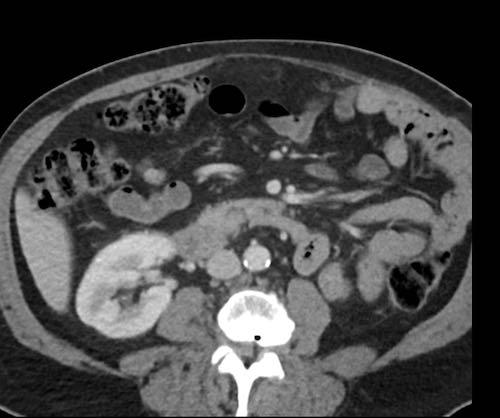

Ca lâm sàng 2

Cuộn qua các lát cắt.

Bạn có thể phát hiện tất cả các tổn thương cấy ghép phúc mạc không?